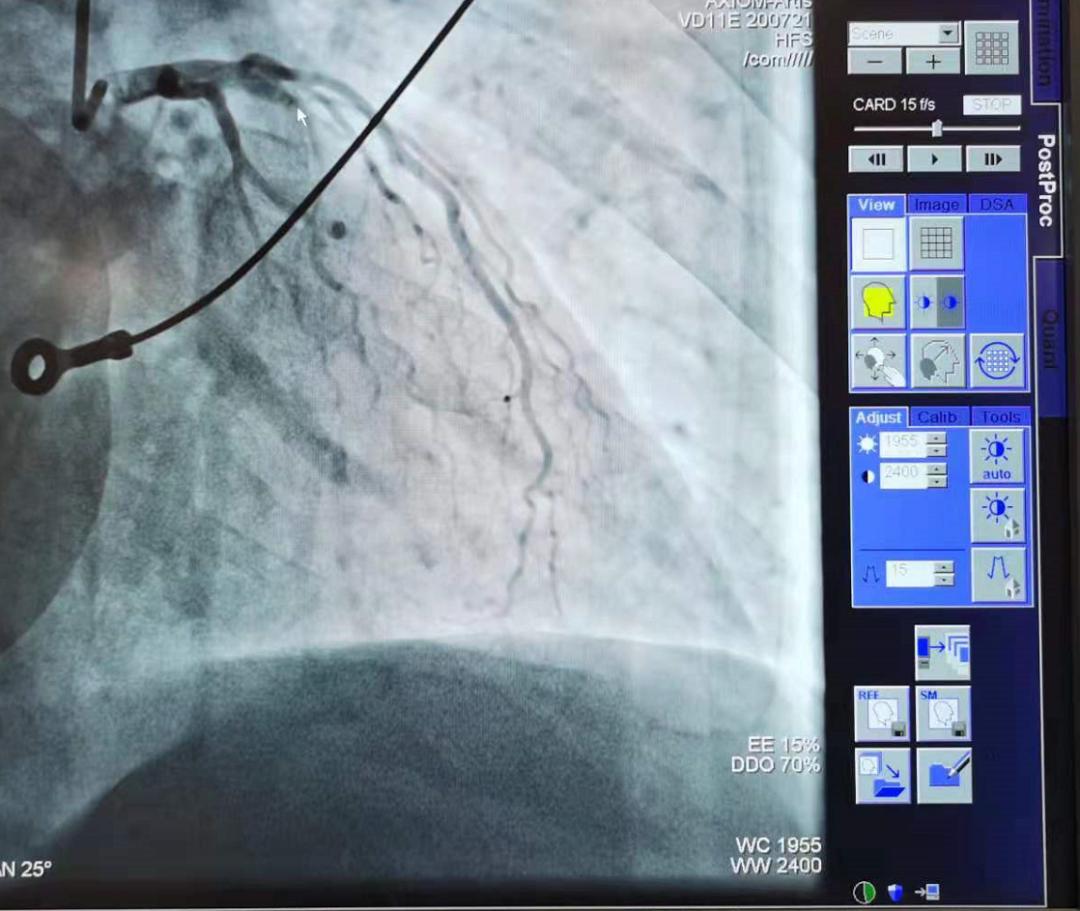

手术前,小李的冠状动脉前降支完全闭塞